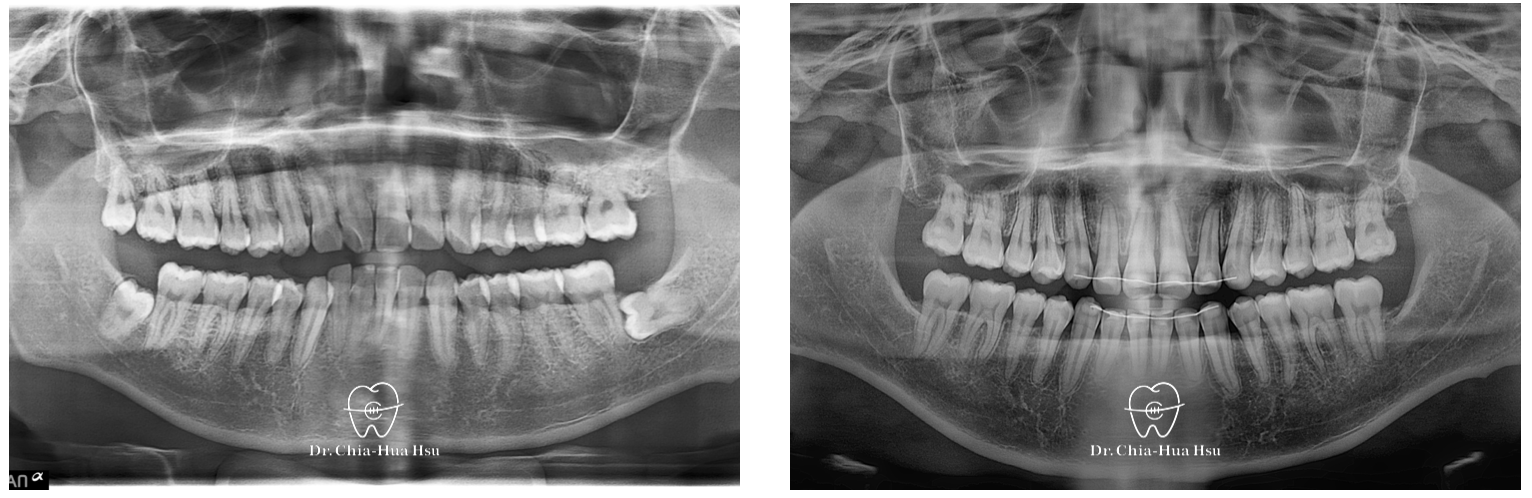

• 問題分析:患者是標準的骨骼一類咬合(Skeletal Class I)伴隨齒列擁擠以及嘴唇微凸,初診時口內有許多牙結石與牙齦紅腫發炎的問題。

• 治療方式:使用傳統金屬矯正器,用骨釘退後齒列獲得空間。

• 治療時間:2 年。

• 治療結果:齒列排齊。不過因為患者沒有拔牙,因此臉型變化不大。

治療前

治療後